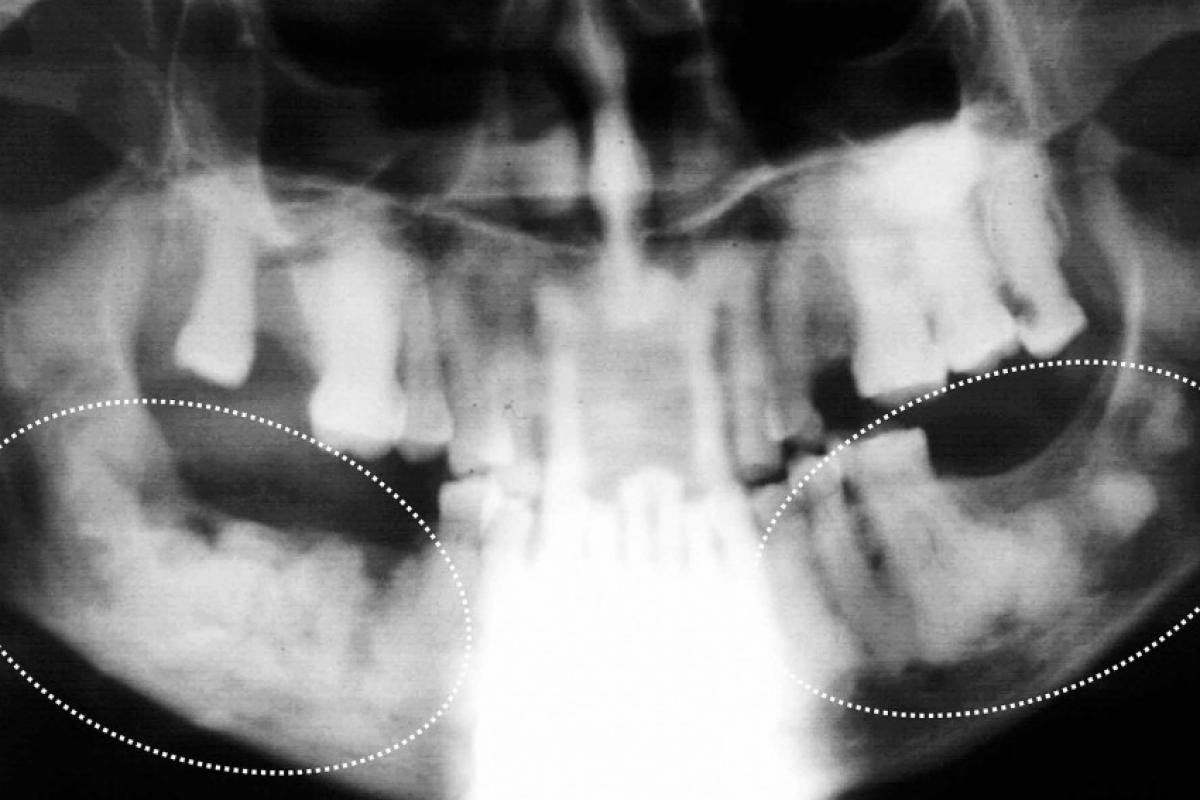

Muitos pacientes com osso denso e desorganizado na mandíbula tem a Displasia Cemento Óssea Florida, muito comum entre nós. Neles, qualquer causa discreta, leva a uma osteomielite superposta com pus e fístulas. Nos maxilares, áreas esclerosantes indefinidas e bilaterais, sem fístulas, geralmente é Displasia Cemento Óssea Florida e não são lesões induzidas por agentes reabsortivos.

Osteomielites maxilares ocorrem em pacientes: 1-Debilitados por alguma doença sistêmica não controlada, incluindo os que tomam bisfosfonatos. 2-Ou com escleroses ósseas generalizadas e bilaterais da Displasia Cemento Óssea Florida que evoluem para osteomielite superposta.